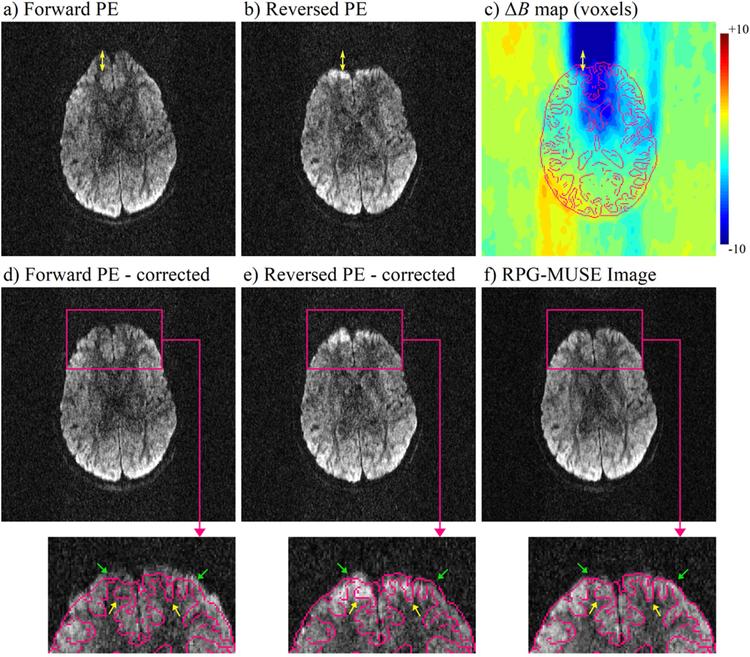

Simultaneous and inherent correction of B₀ and eddy-current induced distortions in high-resolution diffusion MRI using reversed polarity gradients and multiplexed sensitivity encoding (RPG-MUSE)

"Simultaneous and inherent correction of B₀ and eddy-current induced distortions in high-resolution diffusion MRI using reversed polarity gradients and multiplexed sensitivity encoding (RPG-MUSE)" by I. Bruce, C. Petty, and A. Song (NeuroImage, Vol. 183).